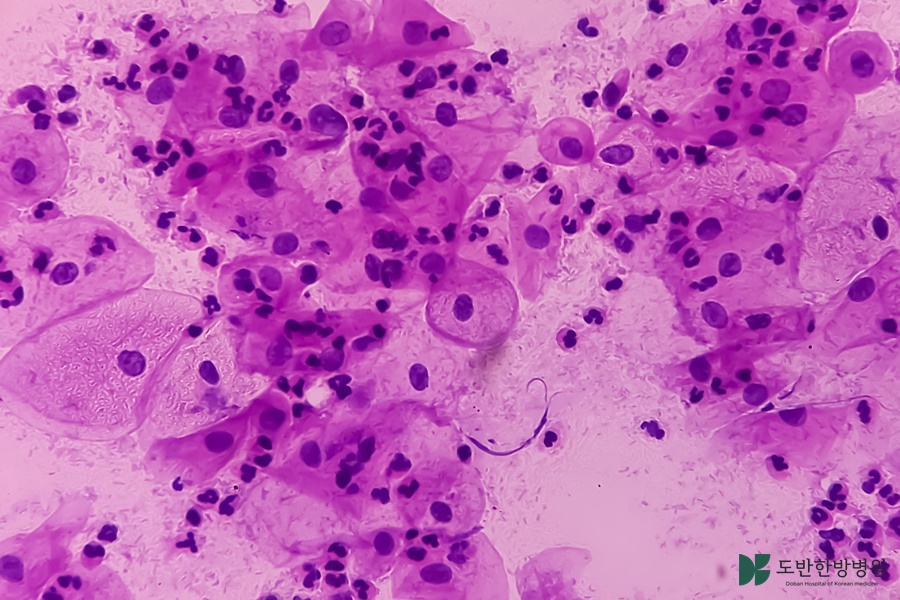

1. 암한방병원은 암 치료를 전문으로 하는 의료기관으로, 전통적인 한방 치료와 현대 의학을 결합하여 환자에게 맞춤형 치료를 제공하였어요. 이 병원에서는 한약, 침술, 뜸 등 한방 치료법과 함께 화학요법, 방사선 요법 등 현대 의학적 접근을 병행하였어요. 암환자들은 통합적인 치료를 통해 신체적, 정서적, 정신적 안정을 도모할 수 있었어요. 이는 특히 치료의 부작용을 화하고, 면역력을 강화하여 전반적인 생활 질을 높이는 데 기여하였어요. 즉, 암한방병원은 환자가 병과 싸울 수 있는 힘을 제공함으로써, 치료 효과를 하고 지속 가능한 회복을 도와주기 위해 설계된 곳였어요.

한방과 현대의학의 조화는 암 치료에 있어 큰 시너지를 낼 수 있었어요. 한방에서는 전통적인 치료 기법을 통해 면역력 증가, 통증 완화, 부작용 감소 등을 목표로 하였어요. 반면, 현대의학은 암세포를 직접 공격하는 효과적인 치료법을 제공하였어요. 두 가지 접근법을 결합하면 환자는 통합적인 관리와 치료를 받을 수 있으며, 개인별 맞춤형 치료 계획을 수립할 수 있는 이점이 있었어요. 이와 같은 조화로운 접근은 환자의 전반적인 상태를 개선하는 데 기여하고, 치료의 효과를 높일 수 있는 기반이 되었어요.